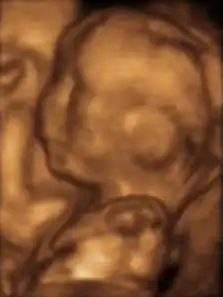

A human fetus, attached to placenta, at three months gestational age

In humans, the fetal stage starts nine weeks after fertilization.[11] At this time the fetus is typically about 30 millimetres (1+14 in) in length from crown to rump, and weighs about 8 grams.[11] The head makes up nearly half of the size of the fetus.[12] Breathing-like movements of the fetus are necessary for the stimulation of lung development, rather than for obtaining oxygen.[13] The heart, hands, feet, brain, and other organs are present, but are only at the beginning of development and have minimal operation.[14][15] Uncontrolled movements and twitches occur as muscles, the brain, and pathways begin to develop.[16]